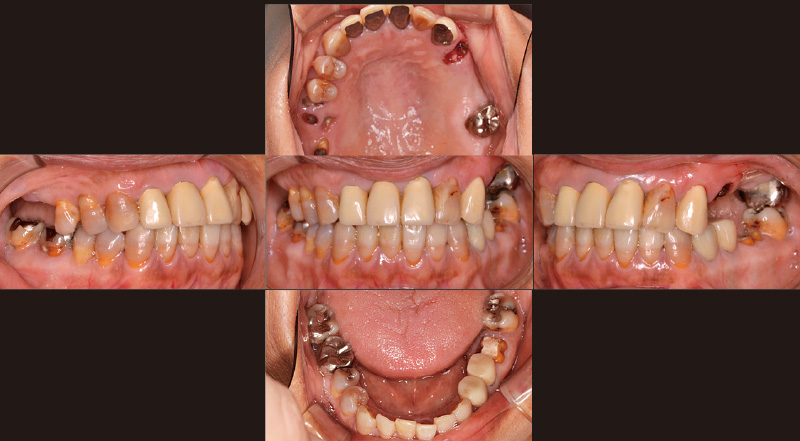

症例の患者さんは「奥歯でものが噛めない」という主訴で初めて来院されました(図1)。義歯治療を行い、いったんは噛めるようになりましたが、噛める位置だけで噛み続けていたためか、徐々に義歯が不安定になり、5年後に再び来院されました(図2, 3)。そこで、義歯を撤去し、インプラント治療に加えて、第一大臼歯まで矯正可能な「iGo Plus」による矯正治療を提案しました。最初に「iGo Plus」のクリンチェック治療計画を行い、矯正治療後の位置を考慮し、インプラント治療の埋入計画を立て、双方の診断画像を照らし合わせ、最終的なインプラント埋入位置を決定しました。計画した位置にインプラントを埋入し(図4)、プロビジョナルを装着しました。その後「iGo Plus」によるクリンチェック治療計画を再度行った後(図5, 6)矯正治療を開始し(図7)、当初の計画通りに矯正治療を完了しました(図8)。ここまでしておけば、噛めなくなる事態は回避できるでしょう。私たちの役目は、咬合状態を回復し、噛める状況まで持っていくことです。その後、審美性を求めて治療を続けていくかは患者さんの判断に委ねます。症例の患者さんの場合は、これから前歯の審美治療を行う方向で相談中です。

図3 2024年2月再診時。趣味であるスキューバーダイビングを行う際、義歯が安定せず、マウスピースがうまく噛めないとのことで、再治療を希望された。 -